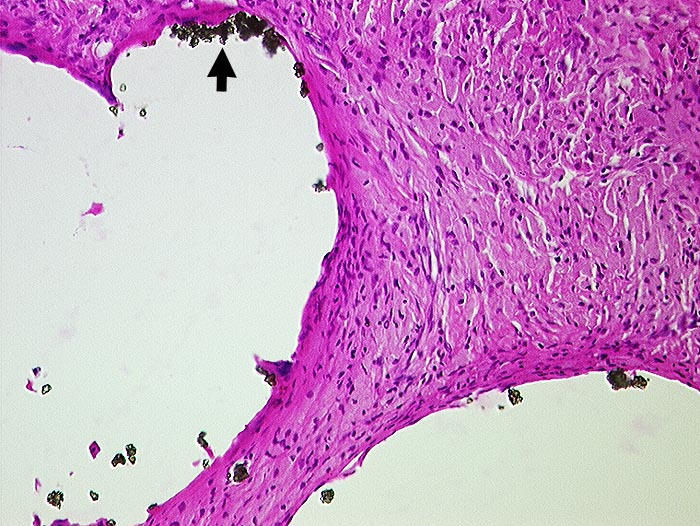

Zementabrieb

Artefakt / Fremdkörper / Pigment

Weichteile Hüfte

Vernarbtes geringgradig entzündlich infiltriertes Gewebe aus dem Pfannengrund. In grossen Hohlräumen liegen Bariumpartikel. Der Zement ist durch die Verarbeitung herausgelöst worden.

Hüft-TP Wechsel.